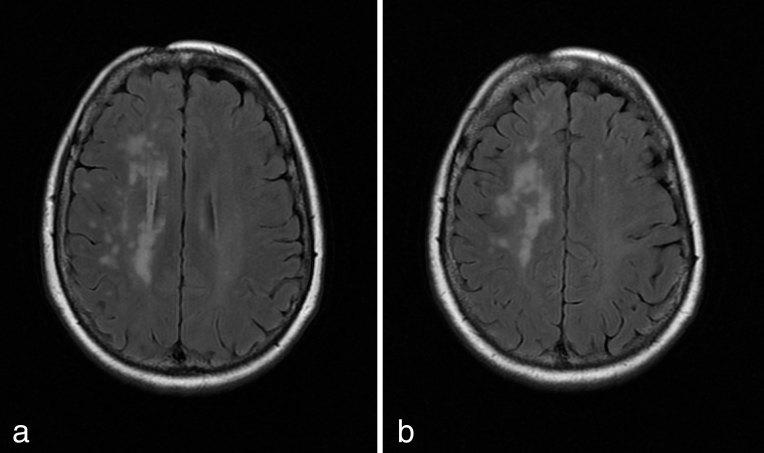

Silent white matter lesion in linear scleroderma en coup de sabre.

J Comput Assist Tomogr. 2008 Sep-Oct;32(5):822-4. doi: 10.1097/RCT.0b013e318153fd60.